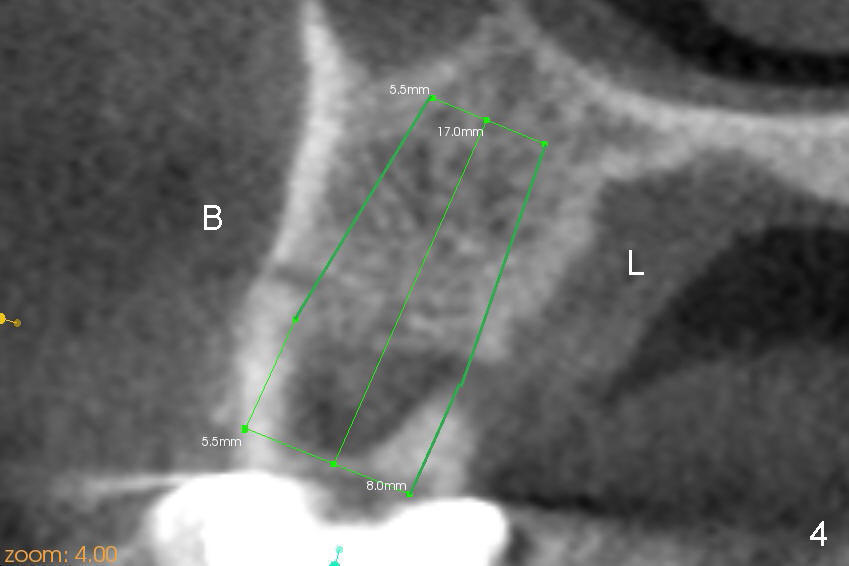

The tooth #3 of a 41-year-old lady is peirodontally compromised (Fig.1 (trimmed panoramus), 2 (PA)) with a large bony defect with the neighboring tooth (Fig.2 *). A large immediate implant is planned to be placed in the basal bone (7 or 8x17 mm, green box) to increase primary stability and reduce the amount of the bone graft to be used (Fig.3 (CT sagittal section),4 (coronal)). If the immediate implant is placed first, there is a limited space (Fig.3 arrows) to place bone graft (red circles) in the hidden areas. Therefore, it would be much easier to bone graft (mixture of autogenous bone, allograft and synthetic bone) first, packed tightly against the mesial, distal, buccal and lingual walls without blocking the entrance to the osteotomy just formed. In spite of the fact that the patient has severe periodontal disease, the bone density of the basal bone is high (Type I/III, Hounsfield units (500-1500)). Reamers will be used to create osteotomy and the autogenous bone will be saved and reused later on.